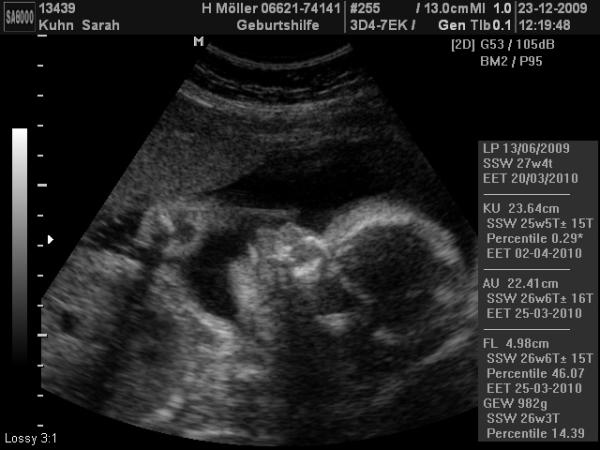

Heute war es endlich mal wieder so weit, heute war VU und mal wieder mit US, ich versuche auch ein bild reinzumachen, aber bis jetzt ging das ja leider nicht, weil ich nicht weiß wie man das umwandelt, aber ich werde es wieder versuchen! Also soweit ist alles in ordnung, er ist zwar etwas kleiner, aber das ist wohl nicht schlimm weils gerade noch so im schnitt ist, liegen tut er in SL (was war SL nochmal???) wiegen tut er etwa 982 gramm KU:23,6cm AU:22,4cm FL:4,98cm Es war mal wieder voll schön, und meine tochter war mit, und durfte ganz fleißig beim schallen helfen, das fand sie ganz toll:) und ich habe echt schon 10 kg zugenommen!!!!echt krass, ich wiege jetzt so viel wie bei lara kurz vor der geburt!!!

freut mich das alles okay is ... und ja das foto hat funktioniert :D für mich sieht das aber schon wie ein strammer bursche aus :D SL=Schädllage .. genau so soll es sein .. der kopf unten .... und es ist toll, wenn man einen doc hat der auch die geschwisterkinder mit einbezieht ;)